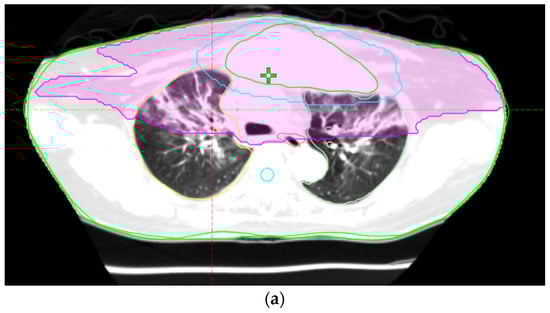

Figure 1.

Chest X-ray showing marked pneumonitis patches, demonstrating increasing bilateral lung infiltration.